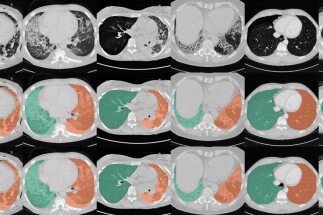

Segmentation Automated segmentation of anatomical structures is a crucial step in many medical image analysis tasks. We show that a basic approach - U-net - performs either better, or competitively with other approaches on both routine data and published data sets, and outperforms published approaches once trained on a diverse data set covering multiple diseases. Training data composition consistently has a bigger impact than algorithm choice on accuracy across test data sets. (Hofmanninger et al, 2020)

The code for lung segmentation is available: code releases